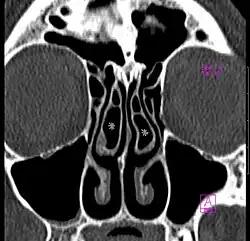

Concha bullosa

Concha bullosa on both sides (marked with asterisks), coronal orientated image from CT

A concha bullosa is a pneumatized (air-filled) cavity within a nasal concha, also known as a turbinate.[1] Bullosa refers to the air-filled cavity within the turbinate.[1] It is a normal anatomic variant seen in up to half the population. Occasionally, a large concha bullosa may cause it to bulge sufficiently to obstruct the opening of an adjacent sinus, possibly leading to sleeping apnea or breathing disorder related to areas innervated by the trigeminal nerve.[2] In such a case the turbinate can be reduced in size by endoscopic nasal surgery (turbinectomy). The presence of a concha bullosa is often associated with deviation of the nasal septum toward the opposite side of the nasal cavity.[3]